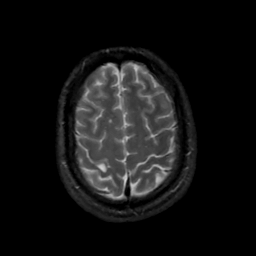

MR Study #12, May 12, 1991 -- Slice #41

[Home][Help][Clinical][Tour 1][Tour 2] Slice 41